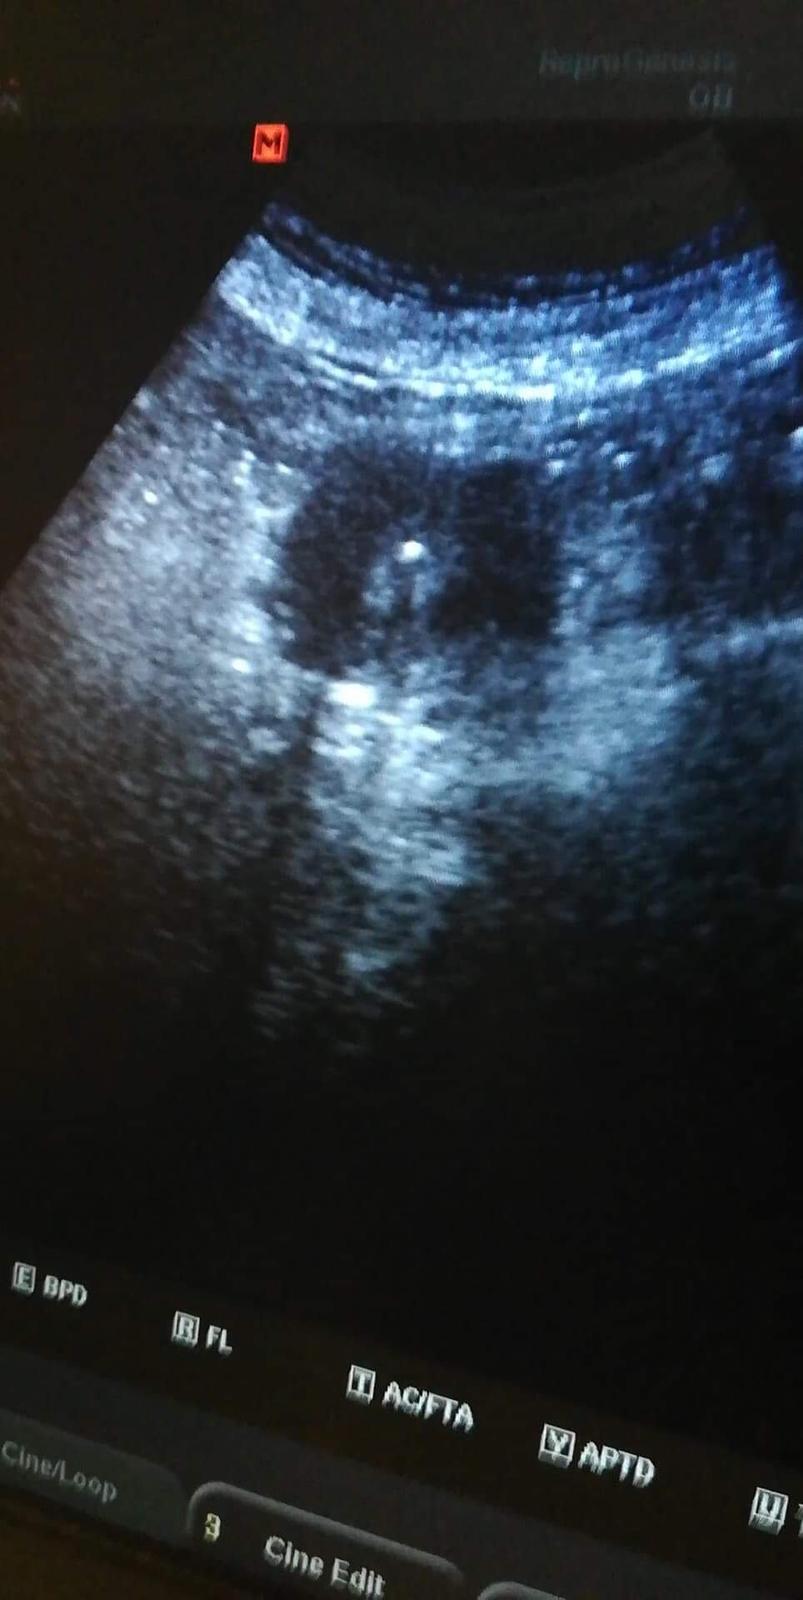

@lucik253 No krása, to bude bojovníků. Ty 2 buněčná, to mělo být asi 12 buněčná ne? ☺️ Jinak já furt ležím, ale už jen lehce špiním, zítra mě čeká ráno ultrazvuk a pokud bude všechno v pořádku, tak propuštění domů. 😊 Doufám, že bude nějakej hodnej doktor a všechno mi pěkně ukáže, hlavně doufám, že se prcek drží a všechno je jak má být. 🙂